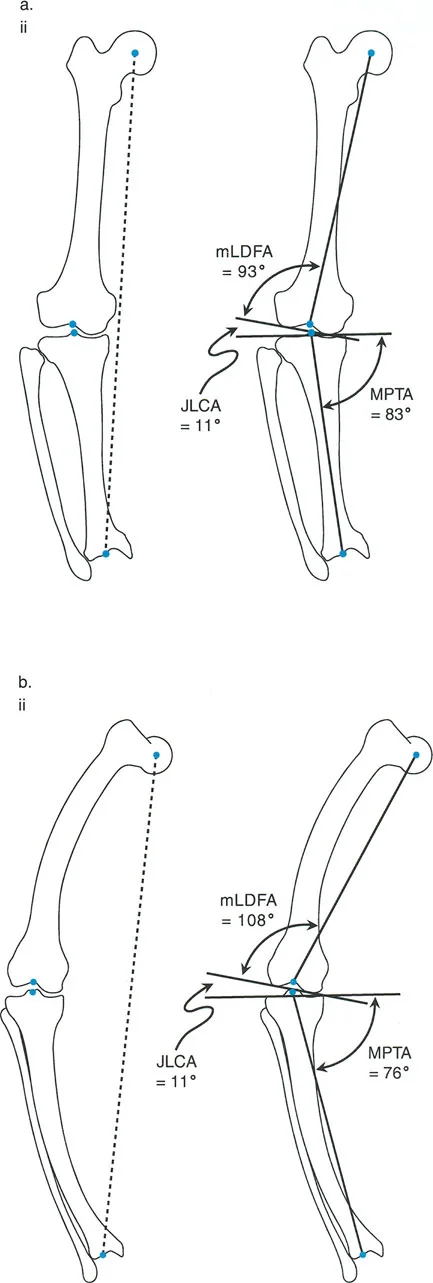

مبادئ بالي لاتجاه المفصل (Paley's Principles of Joint Orientation)

بعد تحديد محاذاة الطرف السفلي (MAD)، يجب على الجراح تقييم اتجاه المفاصل بشكل منهجي بالنسبة للمحور الميكانيكي. لكل مفصل ميل طبيعي يمكن التنبؤ به بدرجة عالية. تشكل هذه القيم الطبيعية الخطوط والزوايا المرجعية التي تُعد متطلبات أساسية للتخطيط قبل الجراحة ولتحديد مركز دوران الزاوية (CORA).

الهدف النهائي لأي جراحة لتصحيح التشوه هو هدفان:

- استعادة المحاذاة الخطية الطبيعية: القضاء على MAD بحيث يمر المحور الميكانيكي عبر مركز الركبة.

- استعادة اتجاه المفصل الطبيعي: التأكد من أن خط المفصل لكل مفصل يقع بزاوية صحيحة بالنسبة للمحور الميكانيكي، مما يمنع قوى القص التي تدمر الغضروف.

زوايا اتجاه المفصل القياسية (بالي):

| اختصار الزاوية | الاسم الكامل بالإنجليزية | القيمة الطبيعية | الأهمية السريرية |

|---|---|---|---|

| LPFA | Lateral Proximal Femoral Angle | 90° (89.9° ± 5.2°) | تقييم تقوس/فحج عظم الفخذ القريب (مثل جنف الورك). يوجه عمليات قطع عظم الفخذ القريب. |

| mLDFA | Mechanical Lateral Distal Femoral Angle | 88° (87.8° ± 1.6°) | يحدد خط المفصل لعظم الفخذ البعيد. حاسم لعمليات قطع عظم الفخذ البعيد (DFO) واستبدال مفصل الركبة الكلي (TKA). |

| MPTA | Medial Proximal Tibial Angle | 87° (87.2° ± 1.5°) | يحدد خط المفصل لعظم الساق القريب. المقياس الأساسي لعملية قطع عظم الساق العالية (HTO). |

| JLCA | Joint Line Convergence Angle | 0° - 2° | يقيم التشوه داخل المفصل، فقدان الغضروف، أو رخاوة الأربطة الجانبية. |